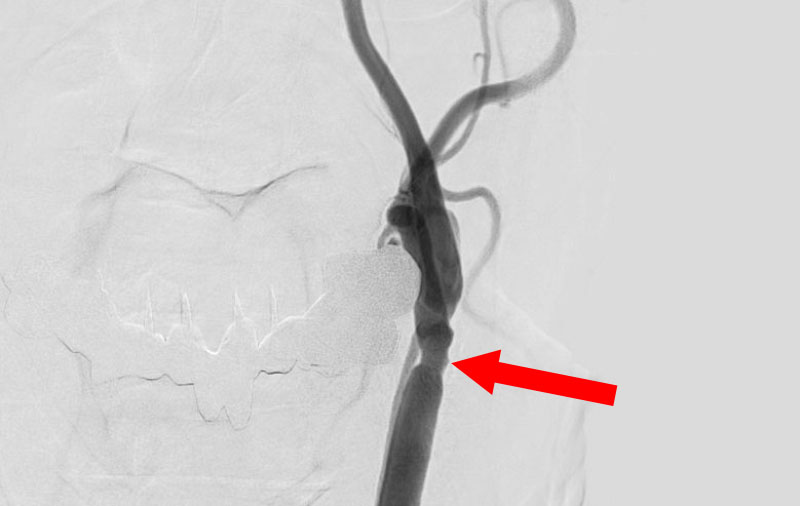

'25年10月

左総頚動脈狭窄症

30代

院内外来

No.1590 手術前

No.1590 手術中

No.1590 手術後